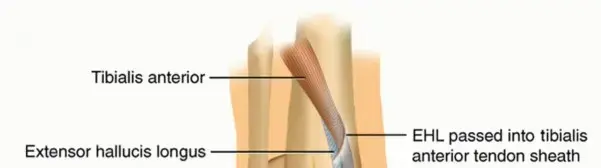

هذه الصورة، التي تُظهر على الأرجح أشعة سينية أو تقييمًا سريريًا قبل الجراحة، تؤكد أهمية التقييم الأولي الشامل في نقص الشظية.